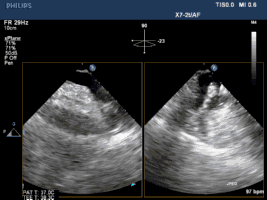

Sentinel CPS系统在另一患者中應用捕抓到的左心耳血栓

左心耳封堵术是对于心房颤动患者的脑卒中预防以及有长期抗凝治疗禁忌症患者有明显疗效。但左心耳血栓为左心耳封堵术禁忌症,以LAmbre 左心耳封堵器于食道超声全程介导下进行手术能克服这一难题,对于左心耳封堵术是一个突破。